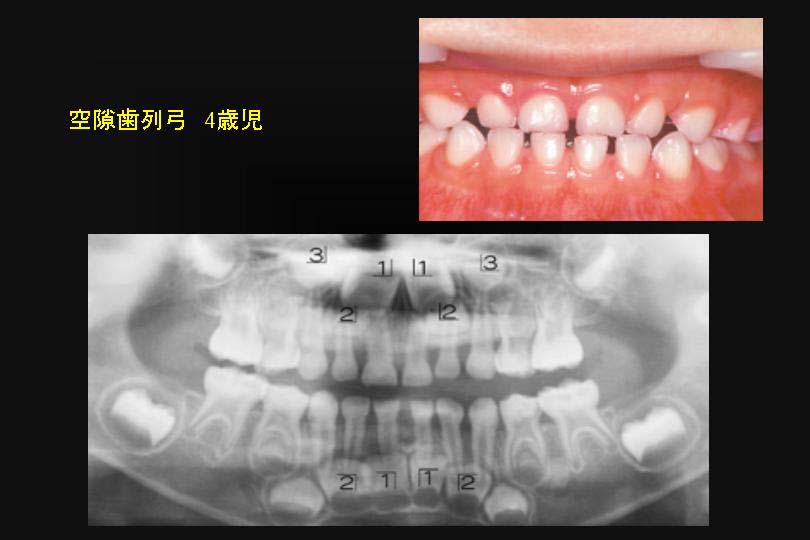

一方、閉鎖型歯列弓では、下顎の永久側切歯は中切歯より大きく写っている。

これは下顎の中切歯より、側切歯が舌側にあることを意味している。(図6)

なんらかの対策が必要だ。

図6

図6:乳歯の閉鎖型歯列弓は、下顎永久側切歯は、舌側へ萌出する可能性が高い。